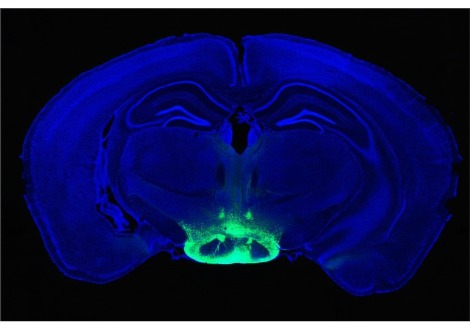

Credit: Rensselaer Polytechnic Institute